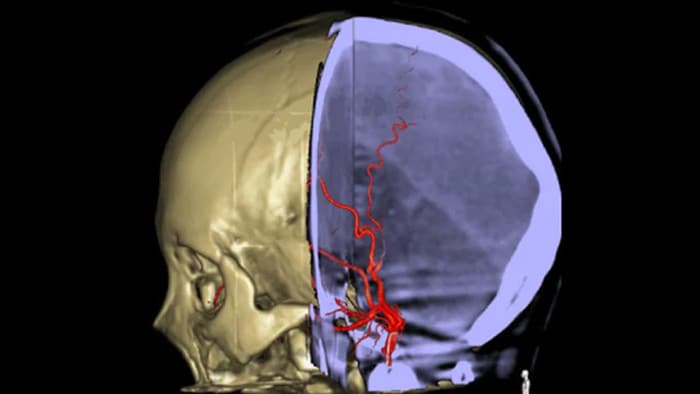

SmartCT Vaso maakt visualisatie buiten het stolsel mogelijk met periprocedurele beeldvorming van de distale bloedvataspecten bij een ischemische beroerte. SmartCT Vaso is een acquisitietechniek op basis van een Cone Beam CT-scan en een intra-arteriële contrastmiddelinjectie. De techniek maakt visualisatie buiten het stolsel mogelijk met periprocedurele beeldvorming van de distale bloedvataspecten bij een ischemische beroerte. Dankzij retrograde vulling worden vaatstructuren voor en na het stolsel zichtbaar. De SmartCT Vaso 3D Roadmap kan worden gebruikt voor het visualiseren van stolselverwijderingsinstrumenten.